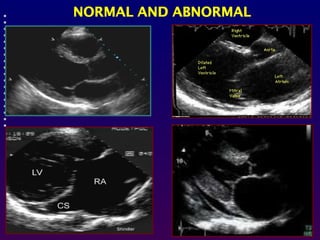

Echocardiography is simply an ultrasound examination of

the heart.During the examination, various different

ultrasound modes or techniques are employed.

-'M' mode produces a graphic tracing of the movement of a

cardiac structure such as a valve leaflet over time.

-Two dimensional echocardiography allows real time

cross sectional imaging of the heart . This technique

provides most of the information regarding the anatomy,

most measurements of the heart.

-Doppler echocardiography uses ultrasound to study the

velocity, direction and character of flowing blood through the

structures of the heart.

Each immage is determined by:

-The transducer position (parasternal, apical, subcostal,

suprasternal) Transducer position is altered by placing

the transducer at various locations on the thorax

-The tomographic view (long axis, short axis, 4- chamber,

5 chamber(.

which is often manipulated by a combination of angulation

and rotation of the transducer from the same position.